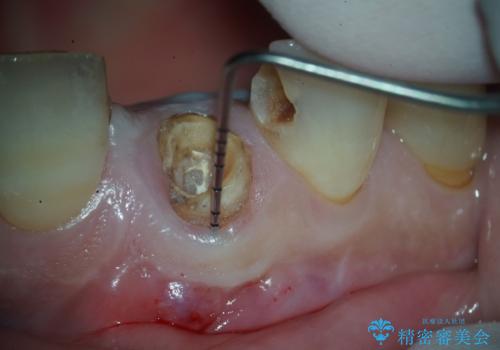

- 右上の前歯(1番)が折れたことを主訴に来院されました。診察とレントゲン検査の結果、歯冠の大部分が失われ、歯根の先には根尖病変(膿の袋)も認められました。残存歯質がほとんどなく、歯を保存することが困難と判断し、抜歯が必要と診断しました。

治療は、まず感染の原因となっていた前歯を慎重に抜歯し、抜歯と同時にインプラントを埋入しました。審美性を重視する部位であるため、骨や歯ぐきのボリュームを維持するための補填処置も併用しています。術後は仮歯を装着し、見た目を保ちながらインプラントと骨がしっかりと結合するのを待ちました。